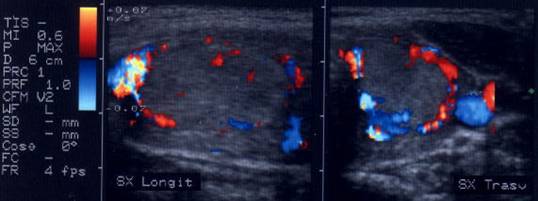

Femeie 25 ani. Nodul unic in lobul stang, contur net, hipoecogen, respecta parenchimul din jur, neomogen, de 18x23x36 mm (7,5 cc).

Citoaspiratia cu ac subtire: nodul adenomatos.

Examen histologic postoperator: adenom trabecular fetal.

Acelasi caz. La doppler color - vascularizatie interna, mai evidenta in powerdoppler.